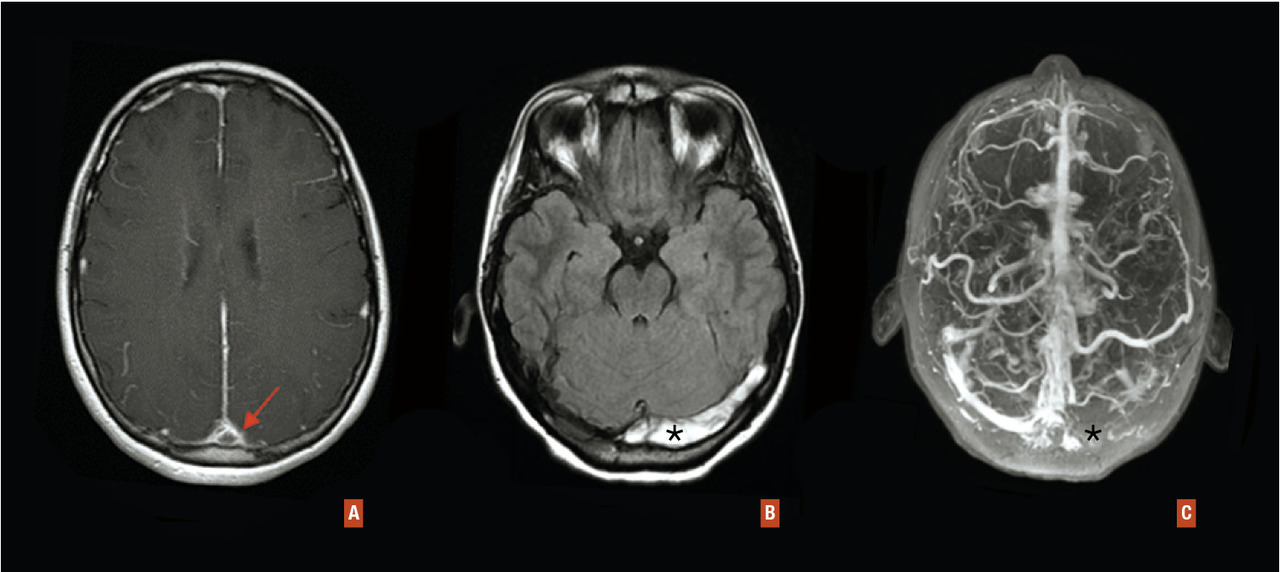

Le diagnostic repose sur l’imagerie des veines et sinus veineux (angioscanner et/ou IRM avec séquences veineuses). L’IRM avec angio-IRM veineuse est l’examen de référence (fig. 2).

Le scanner cérébral sans injection peut montrer une hyper­densité spontanée du sinus thrombosé. Après injection de produit de contraste, il existe un rehaussement de la paroi du sinus alors qu’il y a un défaut de remplissage du sinus, qui se traduit par une hypodensité triangulaire au sein du sinus (signe du « delta vide »). On pourra également voir des signes indirects de thrombose veineuse cérébrale sur le parenchyme cérébral : œdème, prise de contraste, infarctus veineux, hémorragies. Le scanner sans injection est peu sensible, surtout en cas de syndrome d’hypertension intracrânienne isolée (50 % de faux négatifs dans ce dernier cas).

L’IRM cérébrale réalisée à la phase précoce (de J5 à J30) montre un hypersignal T1 et T2 du sinus veineux thrombosé. À la phase très aiguë (< J5), le diagnostic est plus difficile (isosignal T1 et hyposignal T2 normal), et l’angio-IRM veineuse permettra de faire le diagnostic en montrant une interruption du flux. Les thromboses de veines corticales seront plus facilement mises en évidence sur les séquences T2* ou SWI (hyposignal).